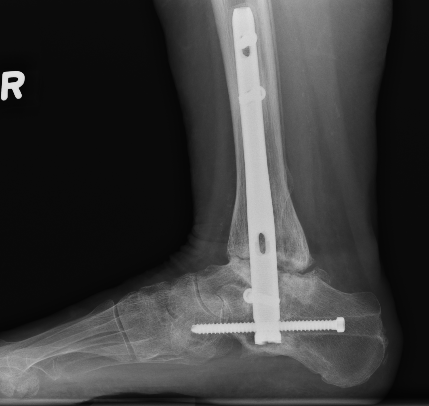

Triple Arthrodesis

www.boneschool.com/triple-arthrodesis

Aim

Realign hindfoot with plantigrade foot

Technique

Lengthen tendoachilles - gastrocnemius recession / release

Lateral approach to subtalar and CCJ / medial approach to TNJ

Remove articular cartilage and prepare joints for fusion

Reduce joints

- Grice maneuver - laminar spreader between anterior process of calcaneus and talus

- check subtalar joint alignment - slight valgus / not neutral or varus

- may need to add medial slide calcaneal osteotomy

Fuse TNJ first to align STJ

Fuse STJ

- may need large lateral bone wedge

- may have issues with lateral skin closure

Fixation - screws / plates / staples

+/- medial osteotomy to allow medial metatarsal weight bearing

- Cotton osteotomy (cuneiform) / first metatarsal osteotomy